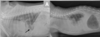

Tracheal hypoplasia on left, normal on right.

50

Tracheal foreign body (tooth) & stomach filled with air due to dyspnea.